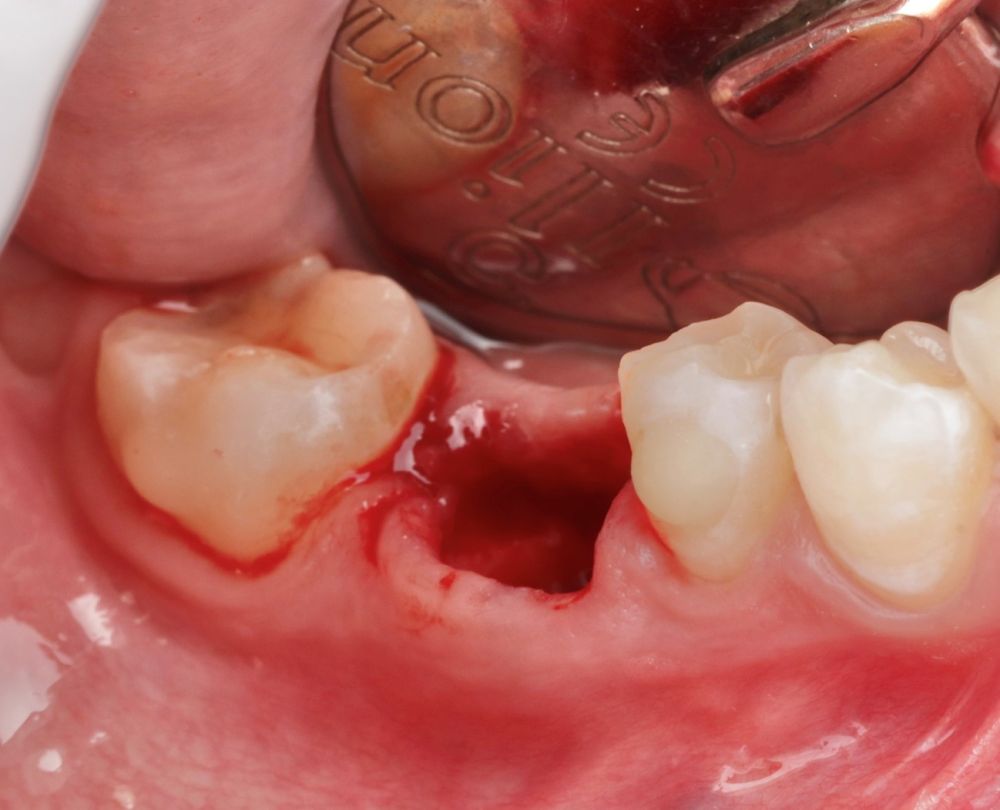

Se reporta el caso de un autotrasplante del tercer molar inferior derecho al alveolo postextracción de un primer molar inferior, en una paciente de 22 años de edad. Actualmente, el autotransplante se considera una opción de tratamiento si se siguen los criterios de selección del caso adecuados, y se realiza una técnica quirúrgica protocolizada. El diagnóstico planificado mediante CBCT, la simulación virtual y la confección de una réplica en 3D optimiza la técnica de forma segura, predecible con tiempos de cirugía menores.

El sitio receptor debe garantizar la adaptación del diente donante, se realizará un diagnóstico mediante planificación con CBCT que permita segmentar virtualmente el diente donante y llevarlo digitalmente al sitio receptor3.

Se requiere un soporte óseo con suficiente tejido queratinizado insertado, sin inflamación y/o infección.